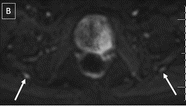

63-year-old with right buttock pain and sciatica for two years, suspected piriformis syndrome. Axial T2 SPAIR (A) image shows asymmetrically hyperintense right sciatic nerve, even better identified on diffusion image (B). On mDixon quant image (C), notice increased fat fraction of the right sciatic nerve vs left (31.5% vs 27.6%) as well as increased nerve area (0.27 vs 0.25cm2). (GIF 6 kb)